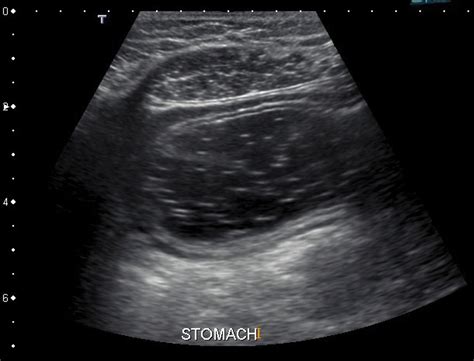

An ultrasound of abdomen is a non-invasive diagnostic procedure that uses high-frequency sound waves to create images of the internal structures of the abdomen. This imaging technique is widely used in medical settings to evaluate various organs and tissues, providing valuable information for diagnosing and monitoring a range of conditions. The procedure is safe, painless, and does not involve radiation, making it a preferred choice for many diagnostic purposes.

An ultrasound of abdomen involves the use of a transducer, a device that emits sound waves and receives the echoes that bounce back from the body's internal structures. These echoes are then converted into images displayed on a monitor. The procedure is typically performed by a trained technician or radiologist and can take anywhere from 15 to 30 minutes to complete.

The patient is usually asked to lie on their back on an examination table. A water-based gel is applied to the abdomen to improve the transmission of sound waves. The transducer is then moved over the abdomen, capturing images from different angles. The images are reviewed in real-time, and the technician may take still images or video clips for further analysis.